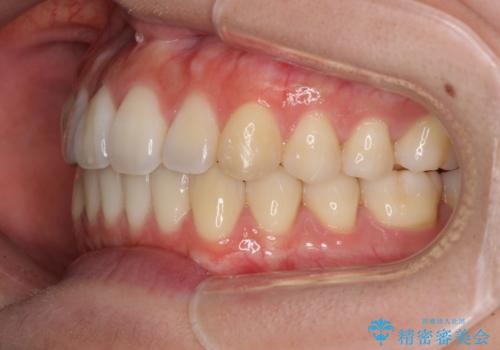

オープンバイトでかみにくい インビザラインによる矯正治療

- 前歯の上下スペースによる食べにくさを気にして来院された患者様です。

インビザラインにより上下の前歯の隙間を閉じていくこととしました。

上下の奥歯を圧下させるようにすることで、前歯を接触させるように計画しました。

上下の隙間に舌が入り込むことがオープンバイトの原因であったため、舌の筋肉のトレーニングも並行して行い、後戻りの抑制を図りました。